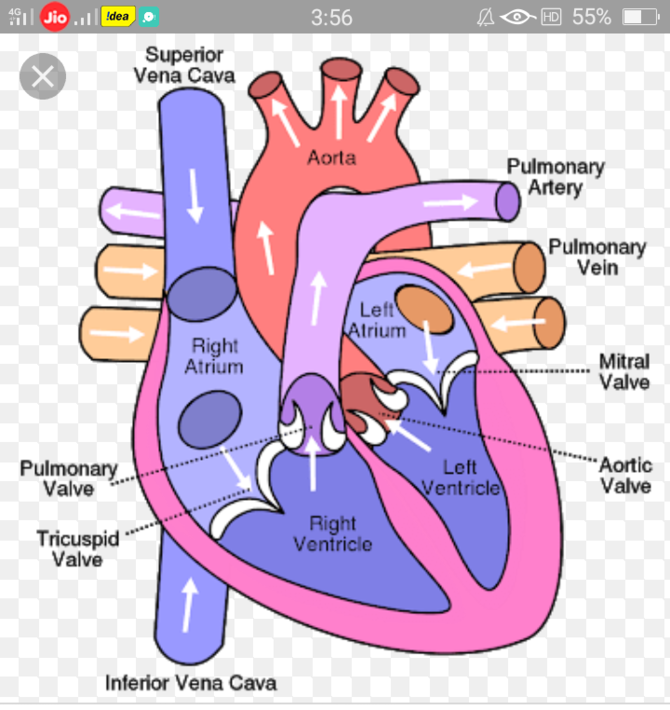

What are the parts that make up a human heart? Diagrams and More | Human heart diagram, Heart

What are the parts that make up a human heart? Diagrams and More | Human heart diagram, Heart  Human heart by kortney16 on DeviantArt

Human heart by kortney16 on DeviantArt  Human Heart-Gross structure and Anatomy - Online Biology Notes

Collection of Human heart clipart | Free download best Human heart clipart on ClipArtMag.com  15 Diagram Of Heart In Human Body | Robhosking Diagram

Human Heart Diagram Without Labels - koibana.info | Human heart diagram, Heart diagram, Human  Human Heart Diagrams | 101 Diagrams

Human Heart Diagrams | 101 Diagrams  Human Heart Simple Drawing at GetDrawings | Free download

Anatomy of the Heart: Physiology | Health Life Media  Human Heart Anatomy Drawing at GetDrawings | Free download

Human Heart - Circulatory System | OER Commons  de Location Of Human Heart In Body mar webmds heart anatomy page provides a detailed image of

Scientific medical illustration of parts of the human heart 685453 Vector Art at Vecteezy  Human Heart Drawing Outline at GetDrawings | Free download

Anatomy of the human heart  Human Heart Drawing Line Work stock vector art 481404348 | iStock